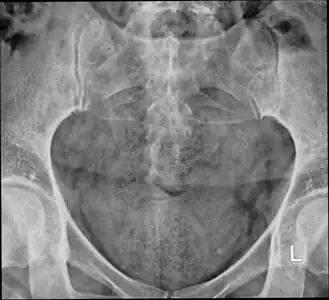

The standard workup of a suspected coccyx fracture includes medical history and a physical examination including a rectal examination.[2] An X-ray is generally not required.[2][3]

-

X-ray -

Lateral radiograph showing a fracture of the coccyx, as well as a lower lumbar fracture

MRI